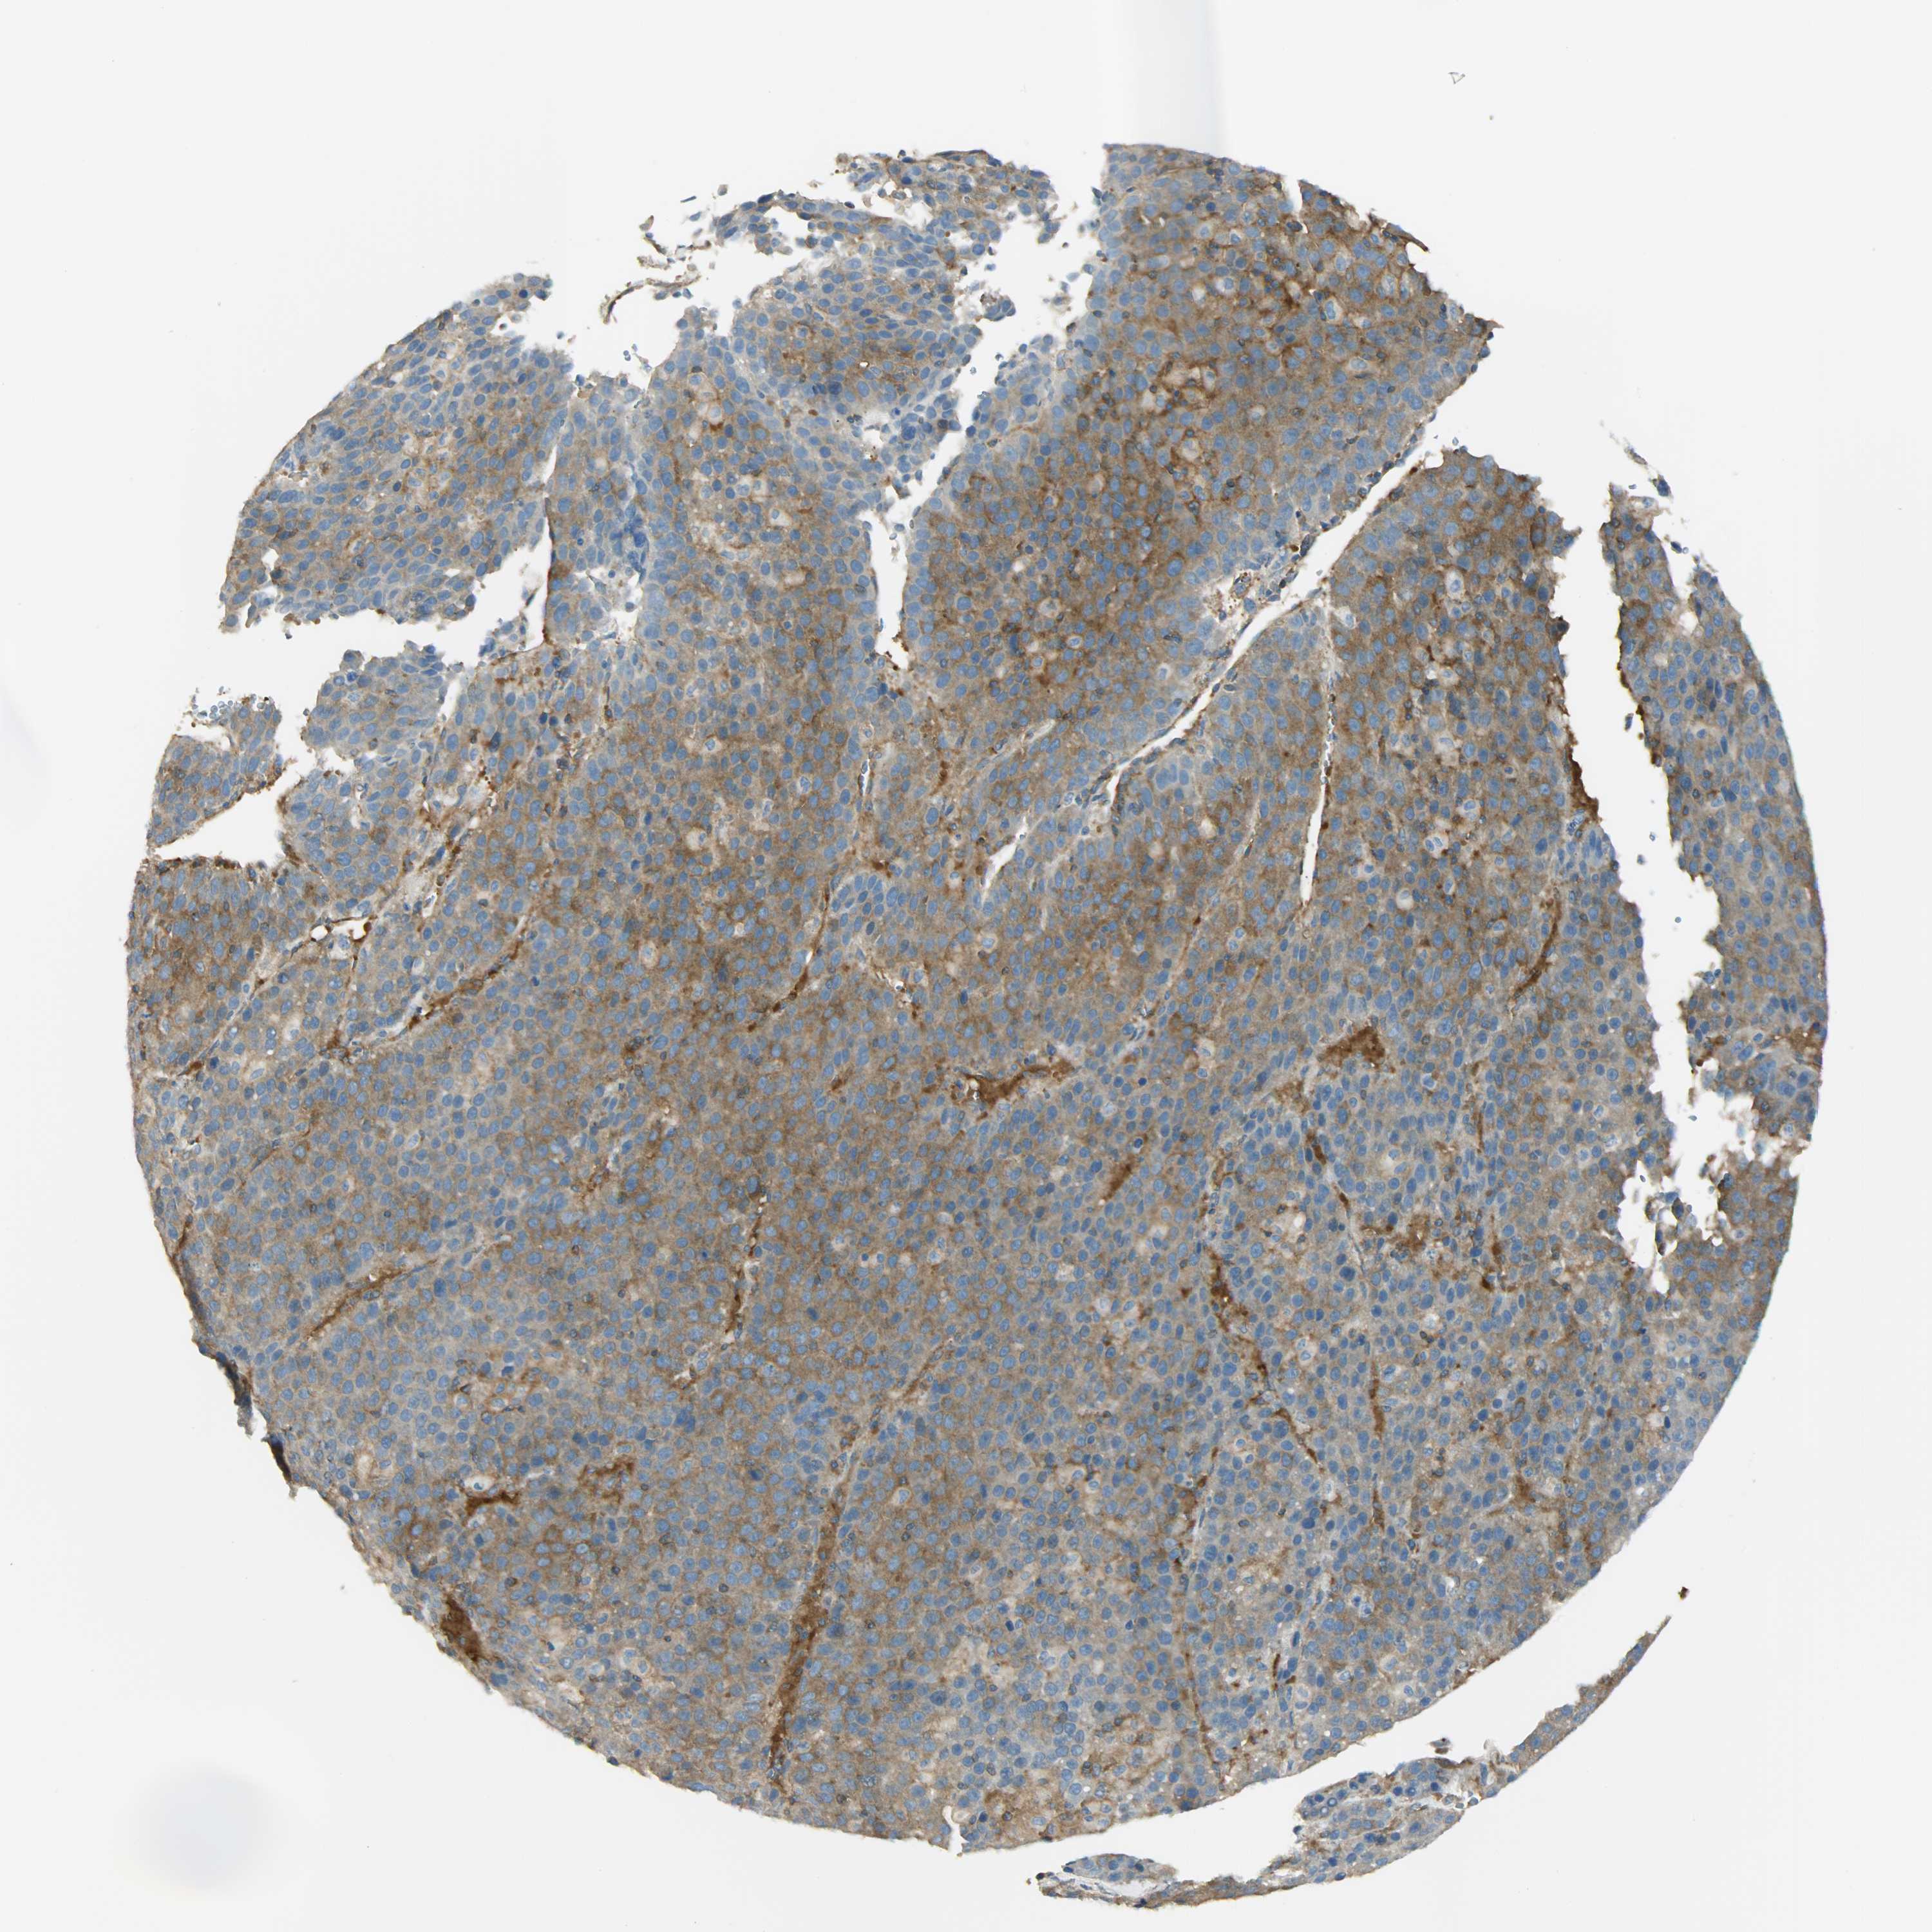

LIVER CANCER - Protein expressioni

A mouse-over function shows sample information and annotation data. Click on an image to view it in a full screen mode. Samples can be filtered based on level of antibody staining by selecting one or several of the following categories: high, medium, low and not detected. The assay and annotation is described here.

Note that samples used for immunohistochemistry by the Human Protein Atlas do not correspond to samples in the TCGA dataset.

Antibody stainingi

Antibody staining in the annotated cell types in the current human tissue is reported as not detected, low, medium, or high, based on conventional immunohistochemistry profiling in selected tissues. This score is based on the combination of the staining intensity and fraction of stained cells.

Each image is clickable and will lead to virtual microscopy that enables deeper exploration of all samples and also displays staining intensity scores, fraction scores and subcellular localization as well as patient and tissue information for each sample.

Antibody HPA004926

Staining

High

Medium

Low

Not detected

Intensity

Strong

Moderate

Weak

Negative

Quantity

>75%

75%-25%

<25%

None

Location

Nuclear

Cytoplasmic/membranous

Cytoplasmic/membranous,nuclear

Cholangiocarcinoma

Carcinoma, Hepatocellular, NOS